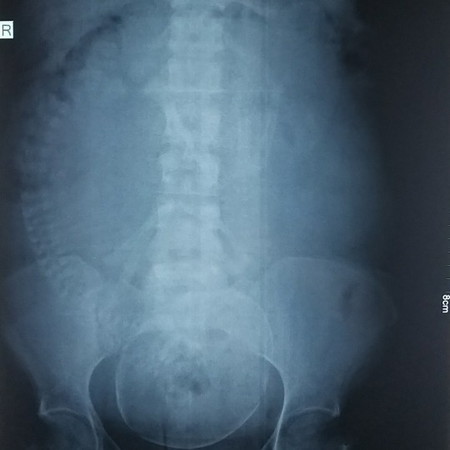

Hello po, sana may makapansin ng tanong ko, ask lng po ako base po sa result ng abdominal xray ko, nasa tamang posisyon ba si baby? Palagay ko kasi nakatagilid siya pero nasa baba naman yung ulo. May risk po ba sa panganganak pag ganito posisyon niya?